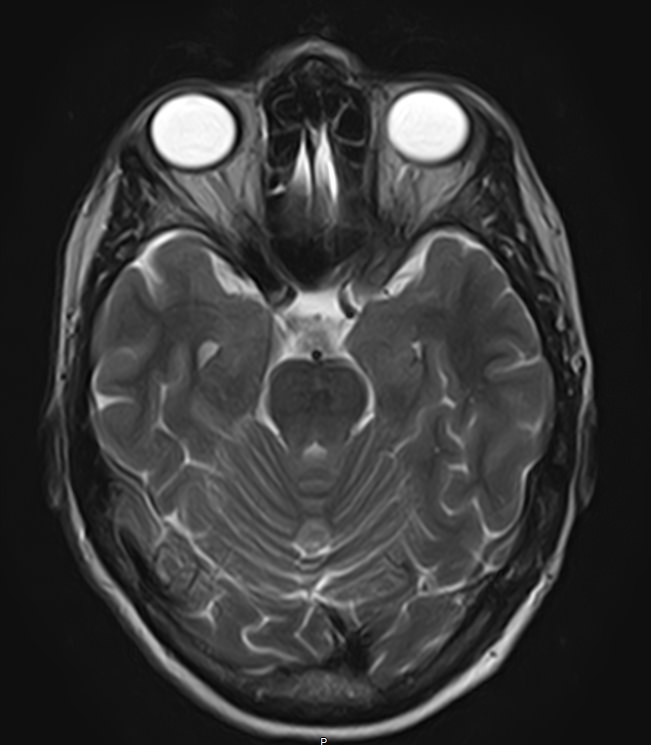

Стандартная МРТ головного мозга дает важную информацию о состоянии и структуре мозговой ткани для выявления большого числа заболеваний, в том числе опухолевых образований, демиелинизирующих заболеваний, воспалительных процессов головного мозга и мозговых оболочек. Стандартную МРТ головного мозга дополняет МР-ангиография, которая отображает состояние системы кровоснабжения головы и шеи. Компьютерная программа обрабатывает данные, полученные при сканировании, и формирует объемные изображения как самого мозга, так и сосудистой системы в отдельности без прилегающих тканей. Обе методики применяются одновременно и взаимодополняют друг друга, давая полную диагностическую картину.

Исследование предоставляет информацию о состоянии тканей головного мозга и оболочек, проходимости кровеносных сосудов, наличии и размерах опухолей, тромбов, гематом и других патологий. Изучив изображения, нейрохирург или другой специалист получает информацию о локализации патологии, степени повреждения тканей мозга, может принять решение о проведении операции либо контролировать ход лечения.